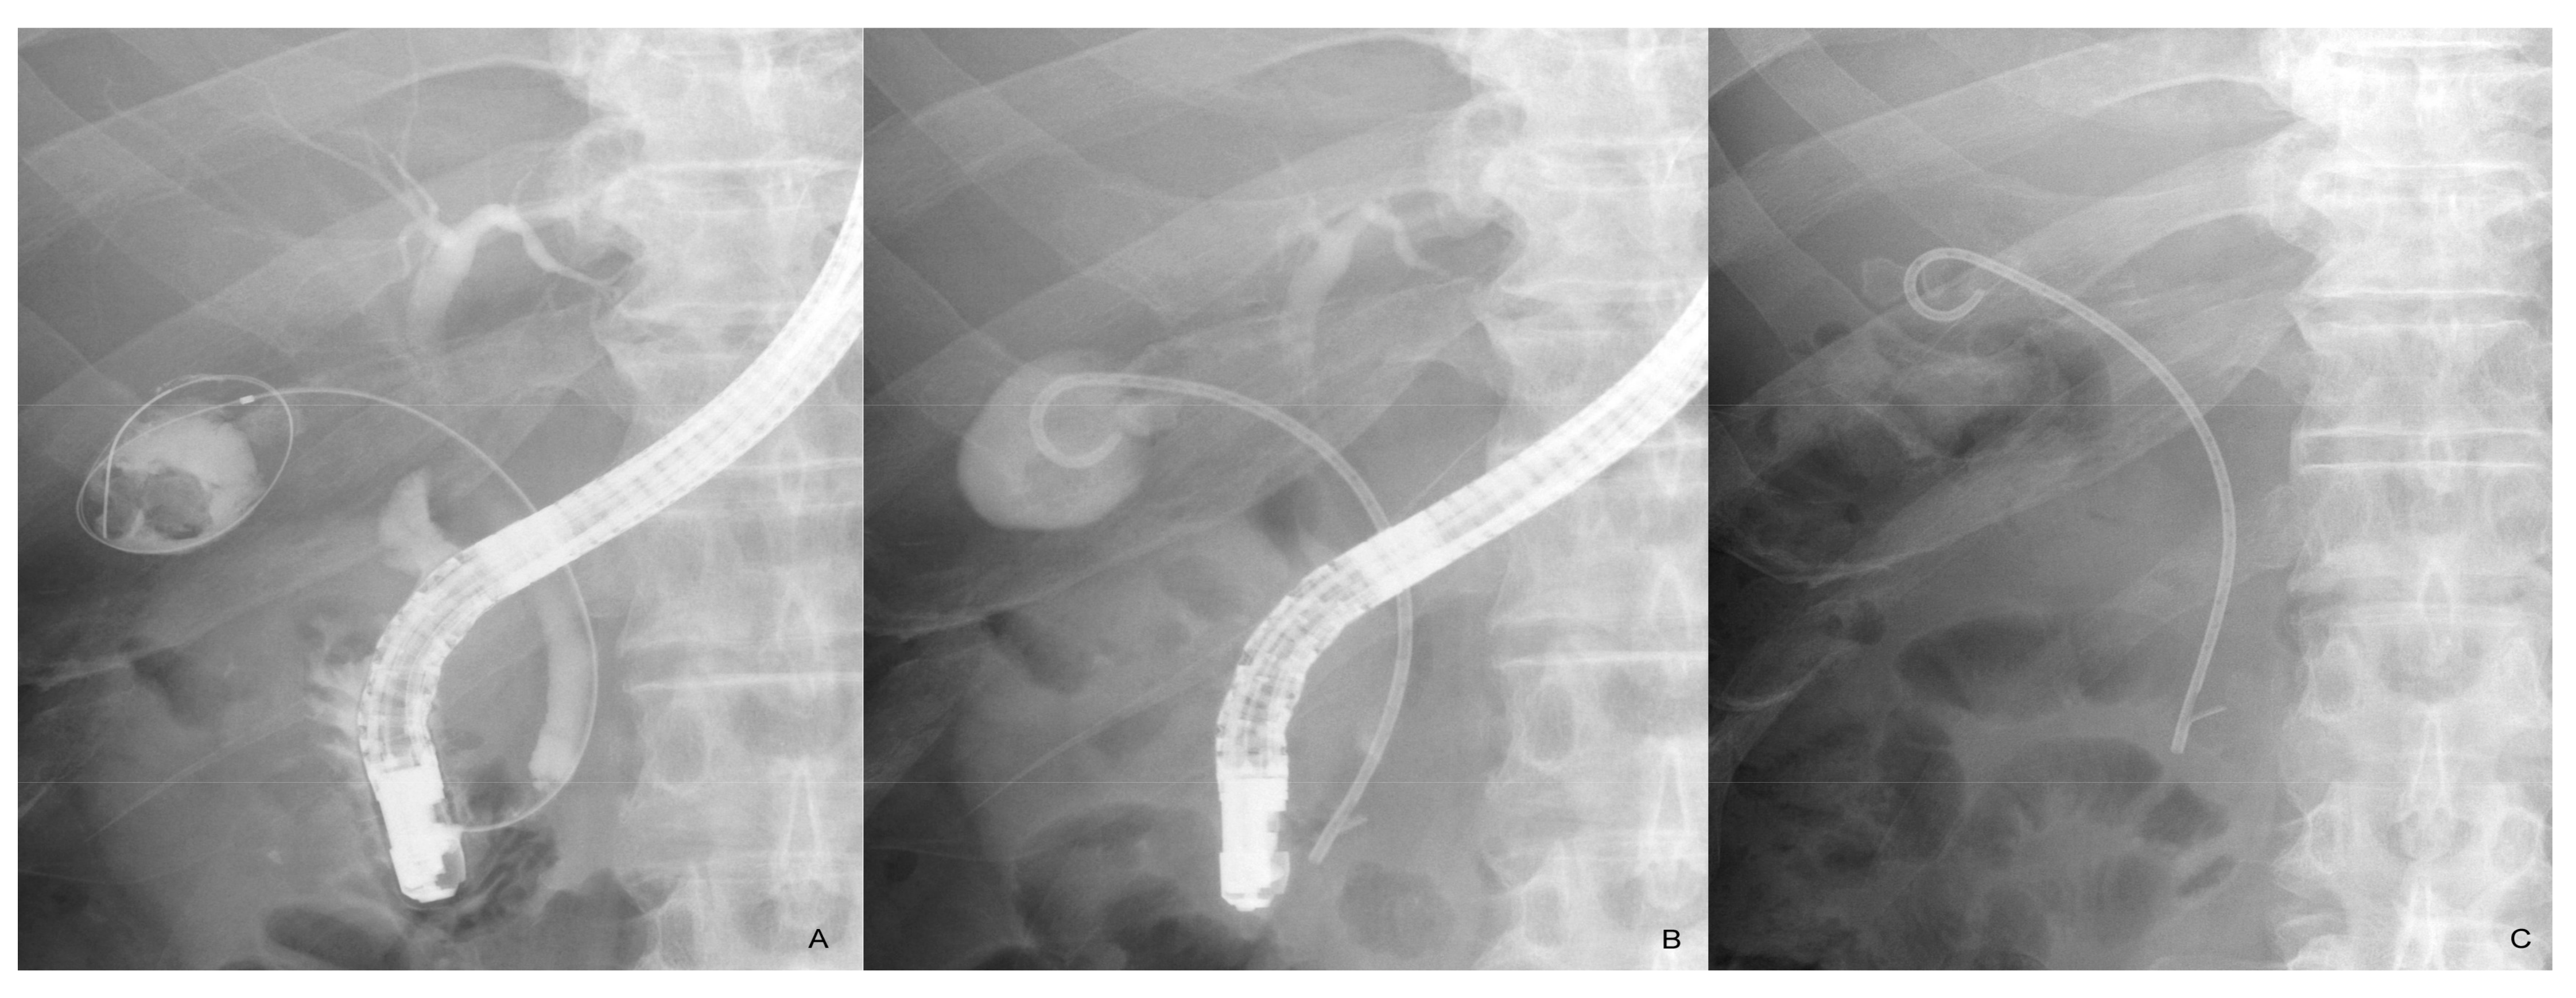

Figure 1.

Endoscopic gallbladder stenting. The cystic duct is sought with a guidewire after biliary cannulation and the guidewire is inserted and placed in the gallbladder (A). A 7 Fr pigtail plastic stent is placed from the gallbladder to the duodenum (B). The stent remains in place 2 years after the procedure with no recurrent cholecystitis (C).